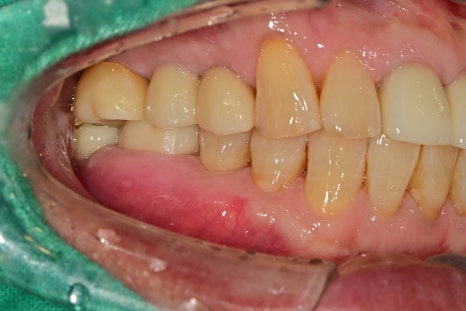

왼쪽 큰 어금니들은 수년 전 발치 상태로 상실되어 있는 상태이고

오른쪽 작은 어금니로 주로 식사를 하고 계셨습니다.

작은 어금니는 저작활동에서 보조적인 기능을 해야 하지만

상기 환자분은 큰 어금니의 상실로 많은 저작력을 받을 수밖에 없었습니다.

다른 부위의 치아에서도 다발성의 치아 마모와 금이 간 것을 발견할 수 있었습니다.